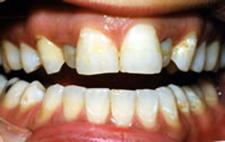

Parodontite moderate

dintii par alungiti datorita retractiei gingivale

pot apare abcese parodontale

halena

mobilitate dentara si diastemizare patologica

pungi parodontale de 4-6 mm

resorbtie osoasa